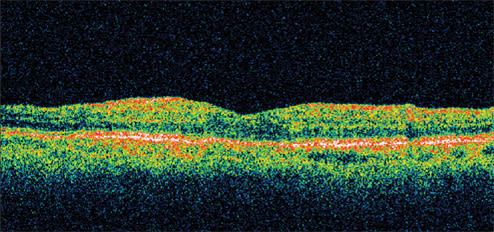

Figure 2. One month after starting treatment with nepafenac 0.1% (Nevanac, Alcon) qid, the patient's vision improved to 20/25 with significant reduction in her retinal thickness.

Presenting visual acuity was 20/40. Her IOP was 23 mm Hg and retinal thickness was 478 μm on OCT (Figure 1). She was treated with nepafenac qid for 6 weeks and tapered over the ensuing 6 weeks. Her vision improved to 20/25 by 1 month with significant reduction in her retinal thickness (Figure 2). By 12 weeks, her visual acuity had improved to 20/20 with a retinal thickness of 216 μm and a normal foveal contour. This represents a reduction in retinal thickness of 262 μm from her pretreatment status (Figure 3). However, she continued to report a mild reduction in contrast sensitivity.